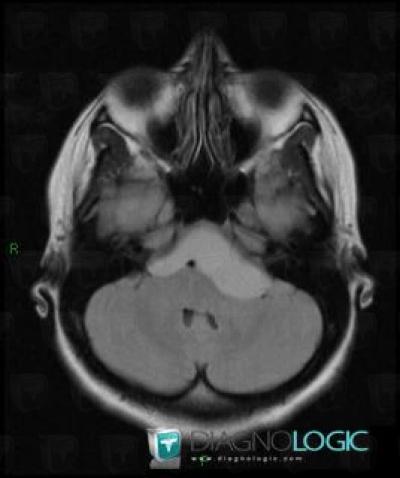

Craniopharyngiome, Espaces peri cérébraux infratentoriels, Fosse postérieure, IRM

Voici les informations spécifiques à l'image clé ci dessus:

- Diagnostic Craniopharyngiome, Localisation(s) Espaces peri cérébraux infratentoriels, comportant les gammes Lésion extra axiale infra tentorielle, Anomalie des citernes de la baseFosse postérieure, comportant les gammes Lésion infratentorielle en hypersignal T2 ou FLAIR